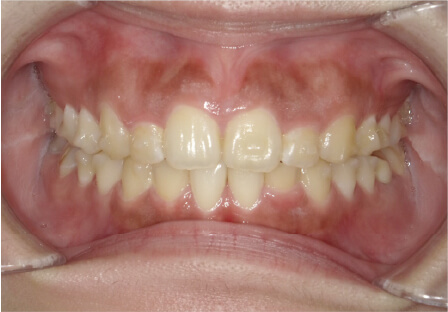

叢生の症例

41歳

/

女性

相談内容

横から見た時のガタガタが気になる

カウンセリング・診断結果

インビザライン、正中は上11に合わせていく、抜歯・拡大装置・IPR・アタッチメントOK

治療内容・方法

アライナー矯正

術後の経過・現在の様子

クリアライナー使用

治療のリスク

痛み・歯根吸収・歯肉退縮・虫歯・後戻り

費用・治療期間

880,000円、7ヶ月

トレーニングなど